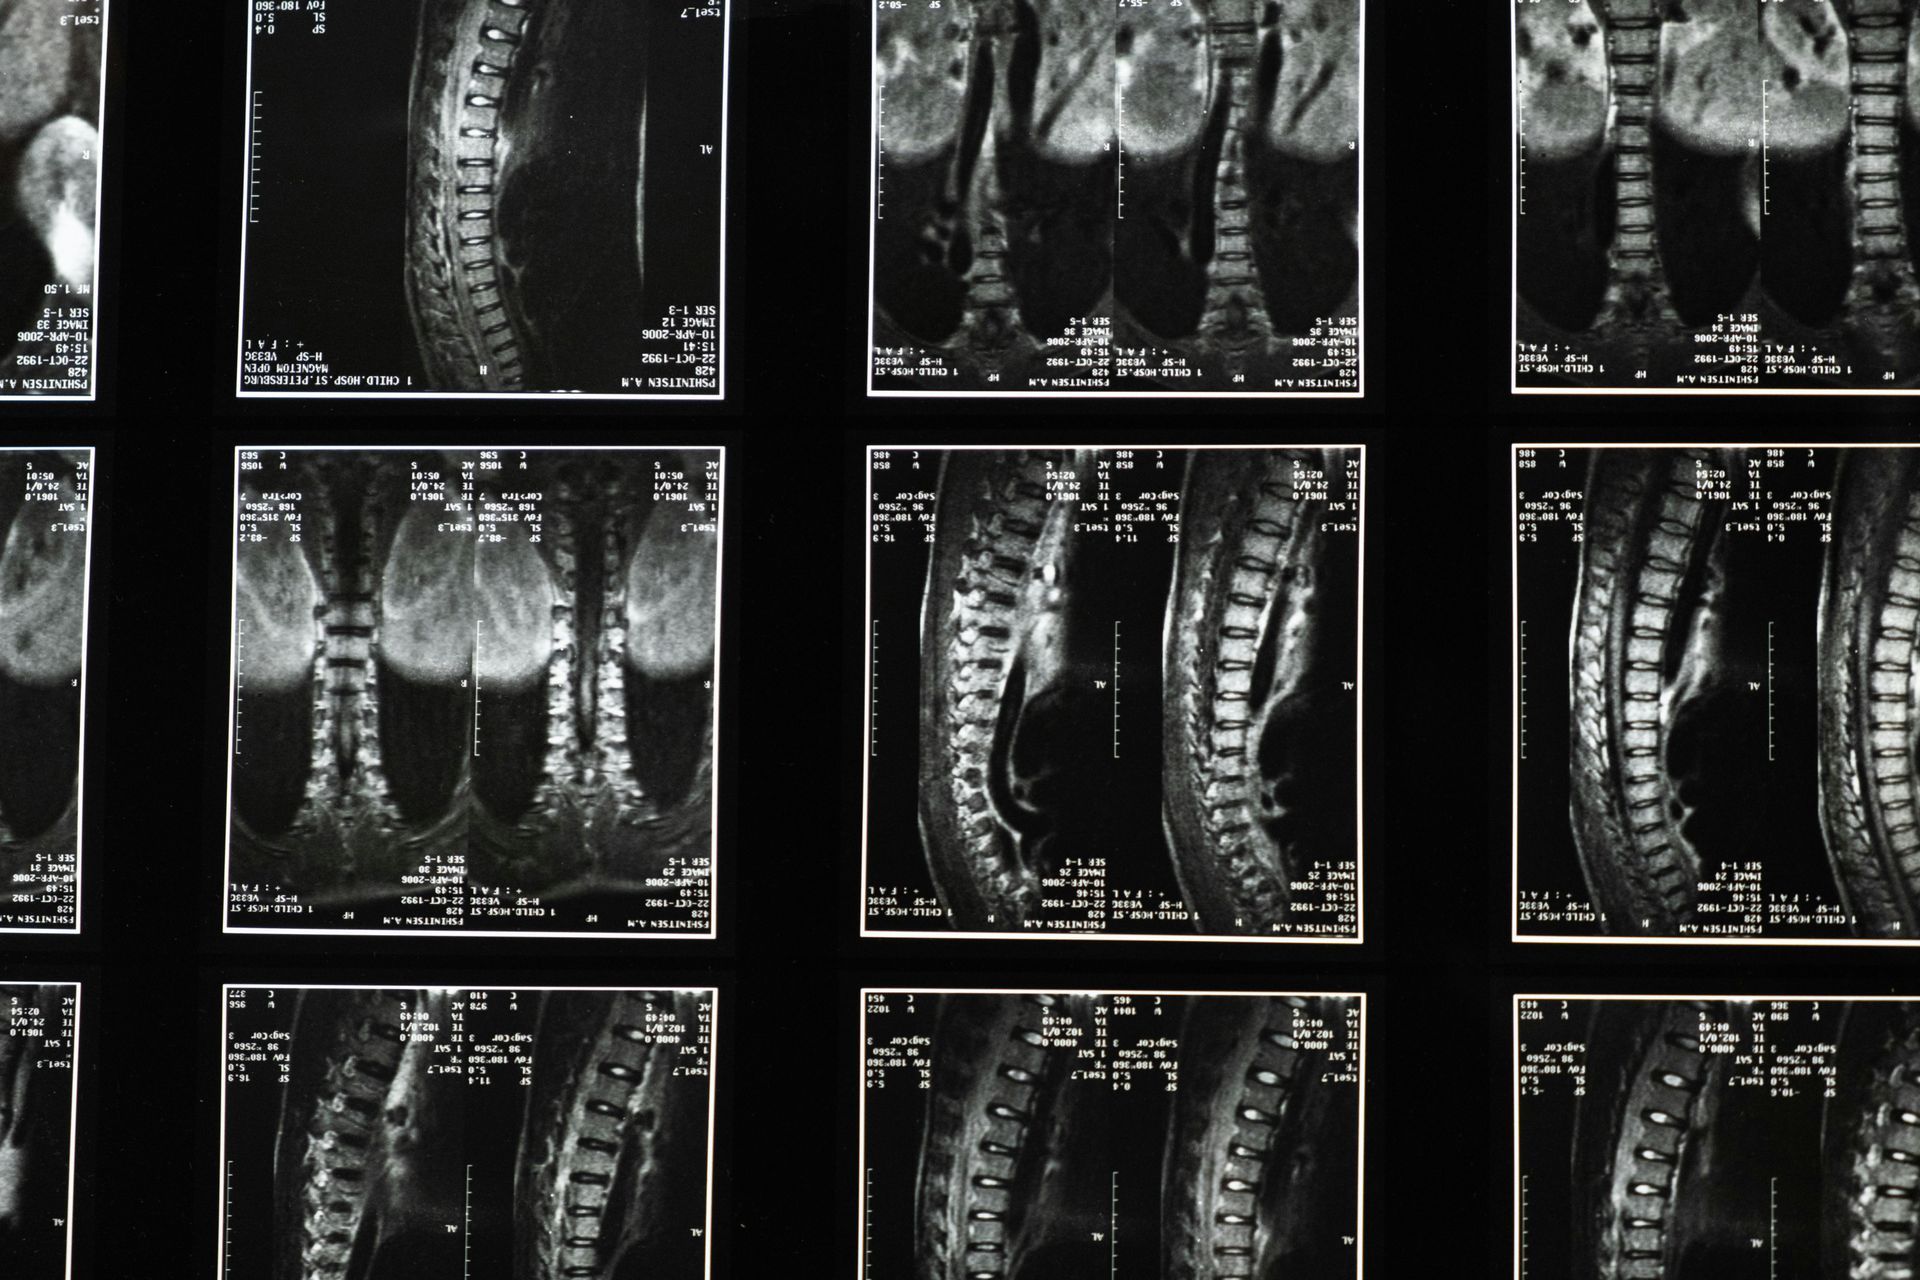

Patologie Spinali: In alcuni casi, fitte alla schiena possono essere causate da patologie spinali come l'ernia del disco o la stenosi spinale. In queste situazioni, è essenziale consultare un medico per una diagnosi accurata e un trattamento appropriato.